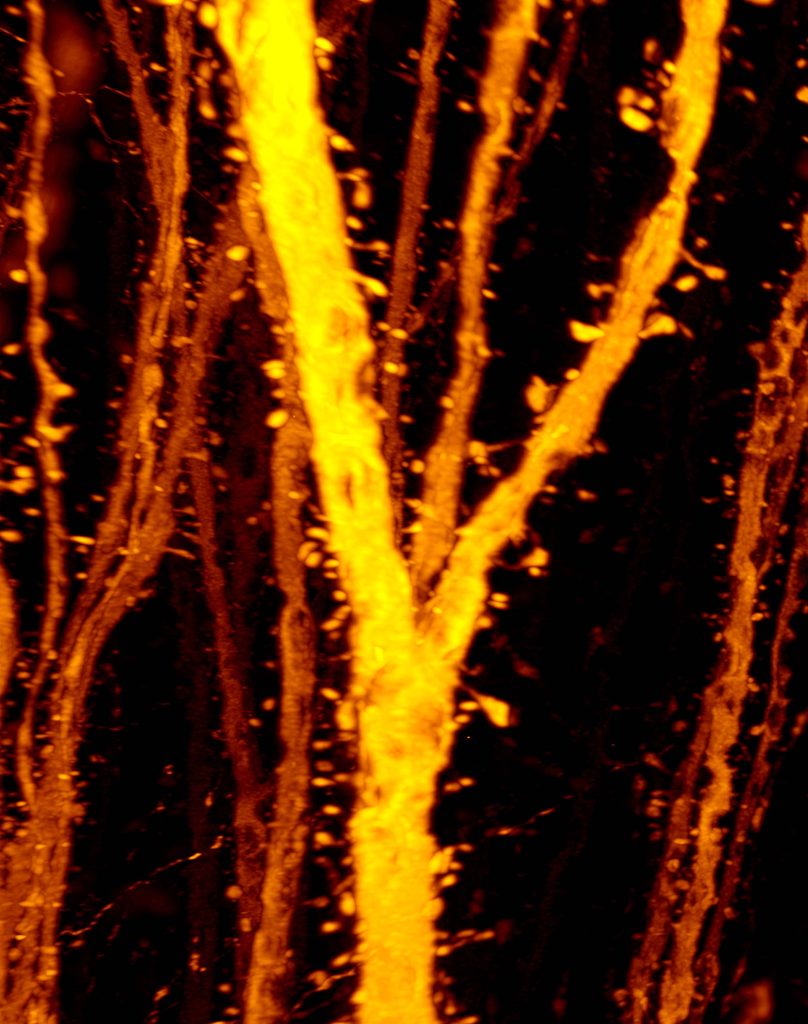

今回の研究では大脳皮質のハブである第五層錐体細胞のシナプス発達を解析しました。従来、思春期にはシナプスが減ると言われていましたが、第五層錐体細胞の特定の領域では思春期にシナプス(樹状突起スパイン)が増えること、この過程が統合失調症のモデルで損なわれていることを解明しました。正常な脳発達のみならず、統合失調症の病態メカニズムに関しても新しい説を提唱しています。